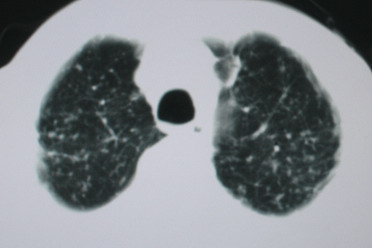

以下是引用卜一在2008-6-3 19:33:00的发言:[br]双肺结节,以双上肺分布为多,期间搀杂片状致密影及索条致密影。考虑:继发性肺结核伴血型播散可能性大。不除外肺泡ca的可能!另:椎体退变!

以下是引用医影拾贝在2008-6-3 18:48:00的发言:[br]双上肺弥漫性小结节影,纵隔窗内钙化淋巴结影,考虑血播性tb可能性较大,不除外肺ca可能

以下是引用panyishengct在2008-6-3 21:09:00的发言:[br]双上肺弥漫性小结节影,纵隔窗内钙化淋巴结影,考虑矽肺或/和tb可能性较大,不除外肺ca可能。腰椎考虑退变。 [br][br]